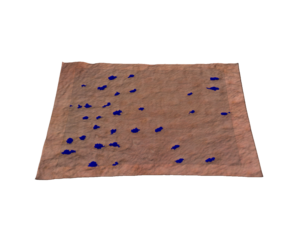

Le C-Cube permet de mesurer le nombre de points noirs et le diamètre moyen. Son champ de vision est constant et calibré, cela signifie que la surface de la photo est toujours la même (1.92cm²). La densité est donc obtenue en divisant le nombre de pores par la surface de 1,92 cm².

Analyse des pores

La production excessive de sébum peut avoir une incidence sur la taille des pores. Ces derniers peuvent se dilater. Grâce à ses mesures dimensionnelles fiables et son calibrage métrique, le C-Cube peut détecter le nombre de pores et les mesurer, en 2D et en 3D.

En 2D, cela consiste en l’analyse des couleurs, suivie par l’identification des formes pour éliminer d’autres objets et conserver uniquement les pores. Les résultats consistent en des images traitées en noir et blanc. Vous obtenez aussi une feuille de calcul avec la zone médiane, le diamètre médian et la densité des pores de chaque image.

L’analyse 3D fournit une dimension supplémentaire de la profondeur des pores. L’approche 3D améliore la sensibilité de la détection des pores. Elle permet alors d’évaluer la profondeur des pores et leur éventuel remplissage.

Image source Image traitée